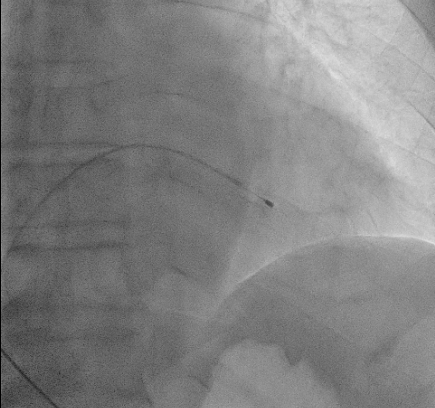

| Transvenous pacing | 중심정맥을 통해 심내막까지 Pacing lead 삽입 | 안정적,ICU 사용 | 감염, 혈관손상위험 |